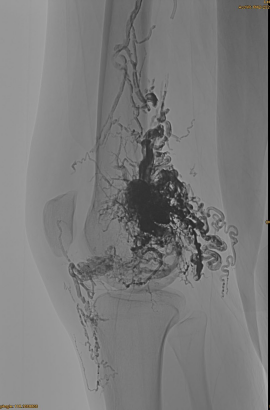

Grunnleggende informasjon om pasienten: Kvinne, 36 år; AVM bekken, hofte, kne, venstre OSG, flere pre - embolisering.

Produkter brukt: 3PCS Lava-34,14PCS Lava-18.

Opprinnelig DSA:

Endelig resultat:

Knapt noen venøs utstrømning:

Sen fase, en annen embo nødvendig, men mye bedre: